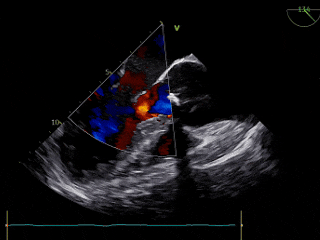

术后TEE评估

TEE超声评估微量瓣周漏,测压差7mmHg,反流改善明显。